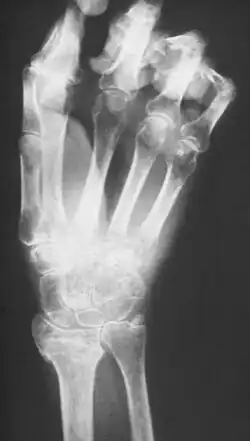

Veränderungen im Röntgenbild

Beim Übergang in das chronische Stadium einige Monate nach Beginn der Erkrankung sind im Röntgenbild meist fleckige Aufhellungen zu erkennen, die durch eine Verringerung des Kalksalzgehaltes im Knochen bedingt sind, wodurch dieser durchlässiger für Röntgenstrahlung wird. Die Entkalkung der Knochen nimmt mit fortschreitender Chronifizierung zu, bis das Bild einer hochgradigen Inaktivitätsosteoporose vorliegt.

Röntgenbild

Im Röntgenbild zeigen sich klassischerweise gelenknahe fleckförmige Entkalkungen. Diese treten jedoch frühestens zwei Monate nach Erkrankungsbeginn auf und können auch völlig fehlen. In späteren Stadien sind die Veränderungen nicht sicher von anderen Knochenatrophien unterscheidbar. Daher spielt das Röntgenbild nur eine untergeordnete Rolle in der Diagnostik.